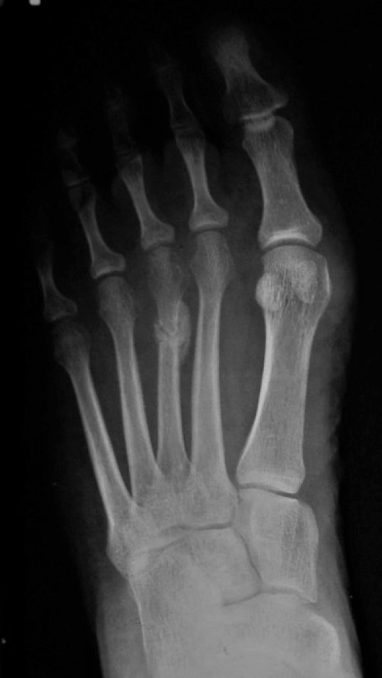

Spiral Fractures

Fracture line is

rotated around the

longitudinal axis of

the bone

The length is at

least twice as long

as the width of the

bone involved